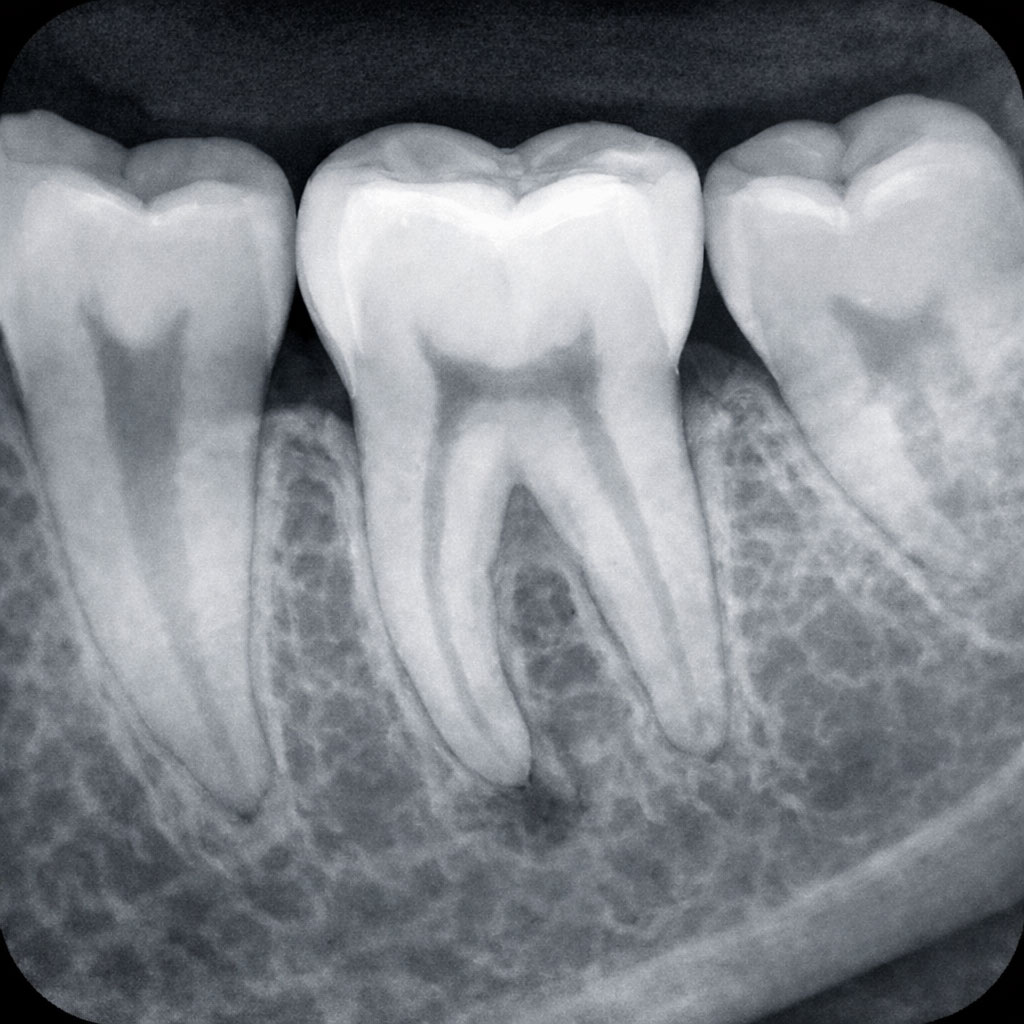

U Dental Scan centru radimo dentalni radiogram – mali rendgenski snimak jednog zuba, izveden pomoću intraoralnih VSP senzora, mekanih fosfornih pločica. Ova tehnologija pruža izuzetno jasne i detaljne slike, a tanki, meki i bežični senzori dostupni u 4 veličine osiguravaju udobnost pacijenta tokom snimanja.

- Kristalno jasne slike – visoka rezolucija za preciznu dijagnozu

- Otkrivanje karijesa koji nije vidljiv golim okom

- Kontrola kvaliteta endodontske terapije (lečenja kanala)

- Praćenje razvoja zuba kod dece

- Procena oštećenja nakon traume

- Kontrola pre i posle hirurških intervencija